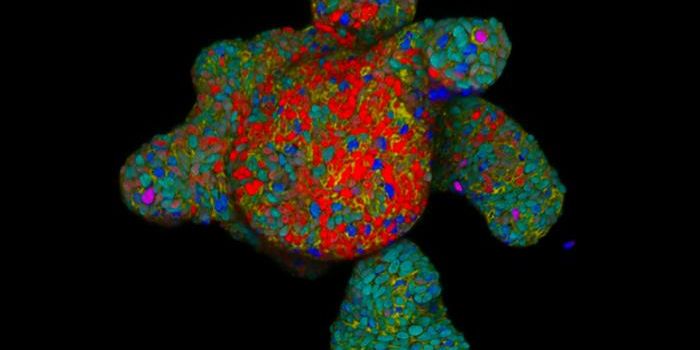

JAN 01, 2025Cell & Molecular BiologyResearchers have developed a method to direct stem cells to form specific structures. By triggering the expression of sp ...